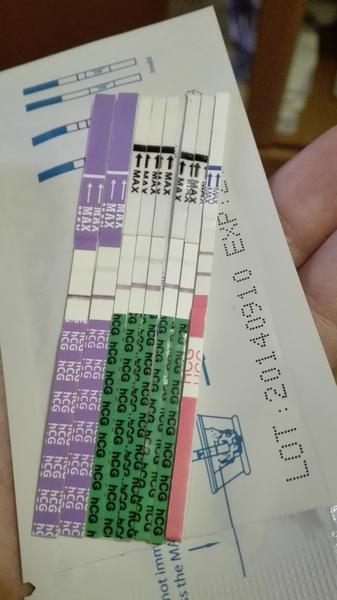

Q: Může domácí těhotenský test (Mamatest, digitální testy) sledovat postup těhotenství?

A: Domácí testy typu Mamatest mohou ukazovat zesilující čárku (v diskuzi byly zmínky o silnější čárce 3 dny po očekávané menstruaci a pozitivním testu při 8 dnech zpoždění), ale tyto testy nezjistí srdeční tep ani přesný růst embrya a nenahrazují ultrazvuk.

- Někteří považují zesilující domácí test (silnější čárku) za uklidňující indikátor, zatímco jiní zdůrazňují, že domácí testy nejsou spolehlivou náhradou za UZ.

- Jak spolehlivé je sledování trendu čáry na domácím testu pro indikaci růstu hladiny hCG?

tak poradnou čarku mam taky až tři dny po očekavane menstruaci a na mamatestu dnes 8 dni spoždení